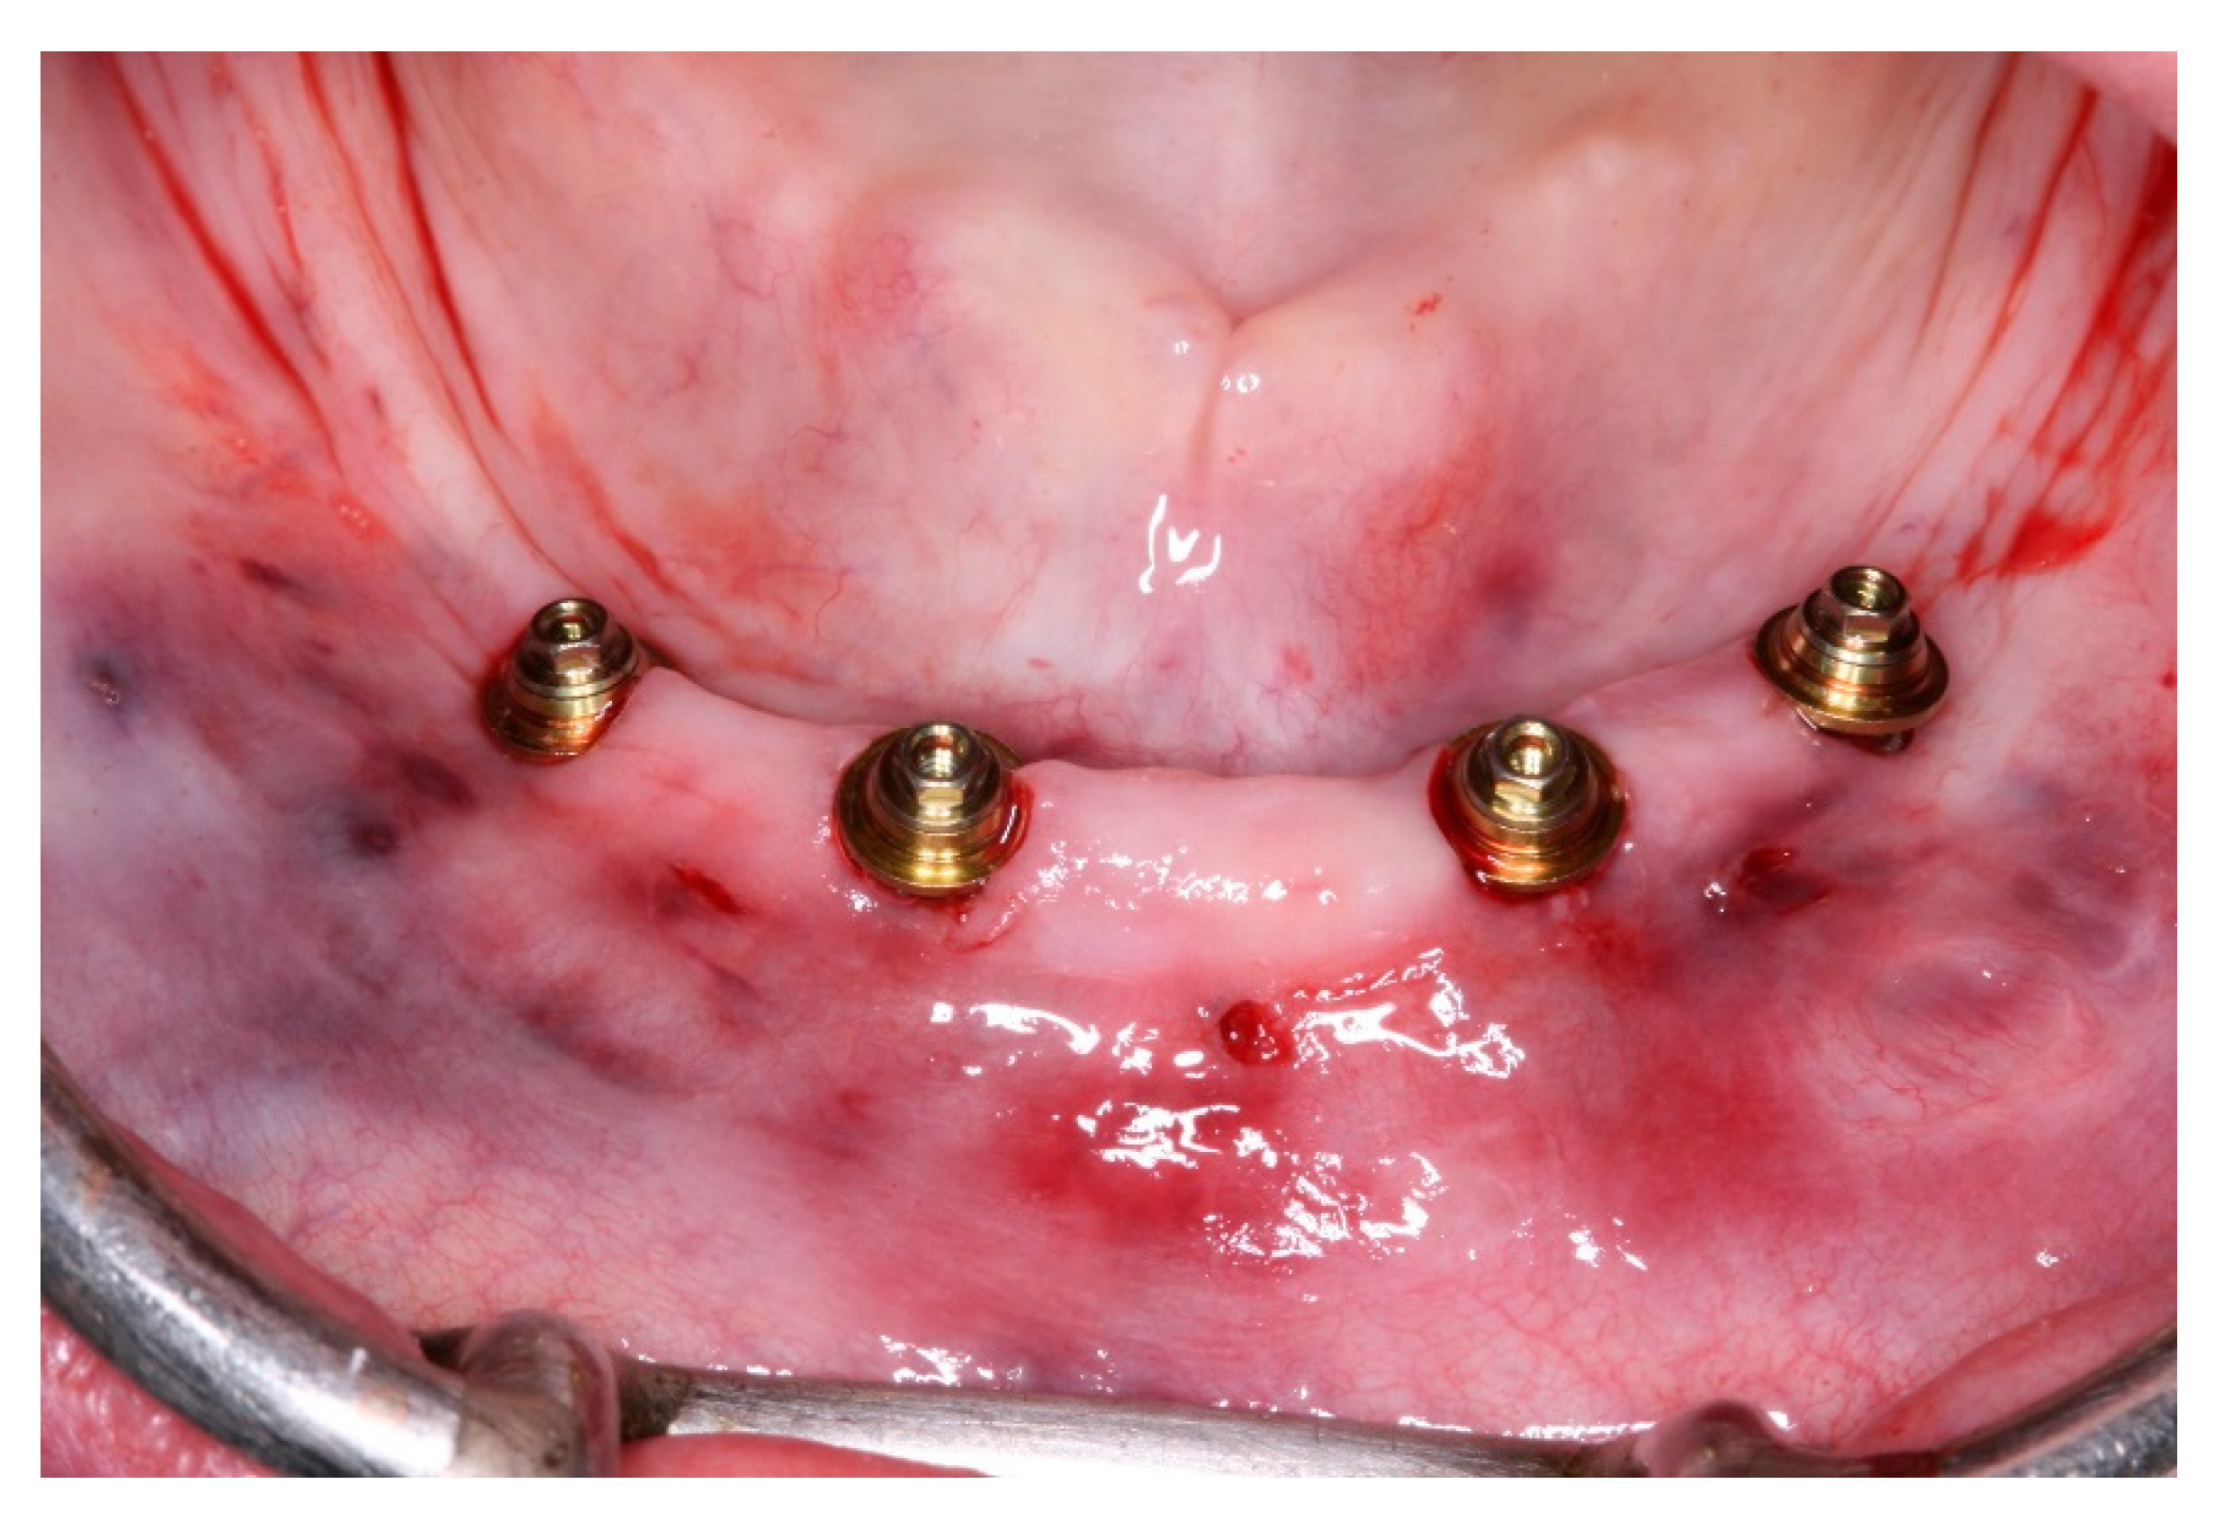

Figure 11. View of the mucosa immediately after surgical guide removal and implants placement.

Figure 19. View of the peri-implants mucosa after 3 months of healing.

Pre-operatory medication consisted only on 2g of Amoxicillin one hour before the procedure, as suggested by her cardiologist. On surgery day, after anesthesia with Articaine 4% 1: 100,000 (DFL, Rio de Janeiro, Brazil), the computed surgical guide was placed in position, assured by the oclusal position on both sides and the stability over the patient’s mucosa, and in this position, fixed with the fixation pins after using their drills, assuring the guide immobilization (Figure 7). After that, we followed the guided bone instrumentation protocol recommended by the Plenum implant system (Plenum® Bioengenharia- Jundiaí, Brazil) to place 4 dental implants of 4.0x10mm with morse-tapper connection, produced by addtive manufacturing technology using titanium powder grade 23 (Figure 8), without raising a flap (Figure 9 and Figure 10). Because of this detail, very little bleeding was noted during the surgery. All implants were inserted with insertion torque ranging from 45 to 60 N/cm, assuring us the possibility for immediate load. The guide was removed (Figure 11) and four mini-conic abutments (Plenum® Bioengenharia- Jundiaí, Brazil), with 2mm high were installed on the implants. No suture was necessary and minimum trauma was noted on the soft tissue (Figure 12). Over these abutments, titanium cylinders were installed (Figure 13) and the lower denture was prepared to capture the implants position, translating the removable prosthesis into a fixed one (Figure 14 and Figure 15). Pattern Resin was used to unite the denture to the cylinders, and over the red resin, pink acrylic resin was used to improve the aesthetic appearance of the prosthesis. The denture was worn out in order not to touch the patient’s mucosa, and to diminish the cantilever we removed the molars from both sides of the denture (Figure 16) and installed the temporary fixed screw retained full-arch rehabilitation (Figure 17 and Figure 18). With this, the patient left the surgical appointment with an immediate load implant rehabilitation. Post operatory medication consisted on 600mg of Ibuprofen, twice a day during 3 days, if necessary. She was instructed to put ice bags on the surgical area during 48 hours, about 15 minutes every hour. On the day before surgery the patient suspended the medication because she had no pain. The patient was also instructed not to sleep with the opposing complete denture for 7 days and feed only with soft foods.

After a healing period of 3 months the patient returned to change que temporary fixed prothesis for a new one, more delicate and with a reinforced metallic bar for a better ferulization of the implants and better dissipation of the stress during function. After removal of the temporary prosthesis we could see the peri-implant mucosa was healthy (Figure 19), without bleeding on probe nor peri-implant sulcus with more than 3mm depth, even around the implants were there were lack of a satisfactory keratinized tissue band, showing us that the patient was being able to maintain the cleansing of the region below the prosthesis. A new fixed rehabilitation over the implants was produced (Figure 20, Figure 21 and Figure 22). 2 years after the surgery we could see on a control panoramic radiograph no signs of bone remodeling above the expected around the implants (Figure 23).